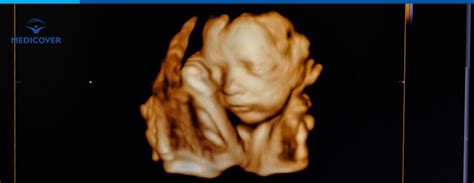

Ecografia morfologică de trimestru I este o investigație ecografică non-invazivă, realizată transvaginal, între săptămânile 11 și 13, 6 zile de gestație. Aceasta presupune o analiză detaliată a tuturor structurilor fetale vizibile, oferind informații valoroase despre dezvoltarea embrionului.

- Translucența nucală (NT): Aceasta este grosimea spațiului subcutanat din partea din spate a gâtului bebelușului. O cantitate crescută de lichid în această zonă poate fi un indiciu al unor anomalii cromozomiale. Valoarea optimă pentru măsurarea NT este între 11 săptămâni și 13 săptămâni + 6 zile de sarcină.

- Osul nazal: Vizualizarea osului nazal fetal în intervalul 11-13+6 săptămâni de sarcină este, de asemenea, evaluată. Lipsa vizualizării osului nazal în această perioadă se asociază cu un risc crescut de sindrom Down și de alte aneuploidii.